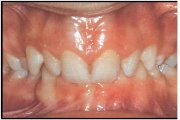

Normaalse jäävhammaskonna pilt küljelt ja eest vaadatuna.